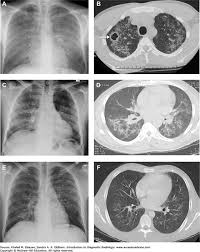

Retrocardiac air space disease. Airspace disease is considered chronic when it persists beyond 4-6 weeks after treatment. Tendency to coalesce near hila. The margins of airspace disease are fuzzy and indistinct.

Air-space opacification is a descriptive term that refers to filling of the lung parenchyma with material that attenuates x-rays more than the unaffected surrounding lung tissue. Consolidation or ground-glass opacity occurs when alveolar air is replaced by fluid pus blood cells or other material. Test results for infl uenza virus respiratory fl uorescent antibodies D3 Ultra DFA Respiratory Virus Screening and In-fectious Disease Kit.

By early detection and proper evaluation of the abnormal retrocardiac shadows the radiologist may establish the diagnosis before the clinical signs and symptoms of compression of large blood vessels and nerves become. Retrocardiac Air Space Disease. Air space opacification is a descriptive term that refers to filling of the pulmonary tree with material that attenuates x-rays more than the surrounding lung parenchyma.

This unusual type of bibasilar atelectasis happens when the lung is trapped as a result of pleural disease while being devoid of air. The opacities tend to be confluent merging into one another. These represent air-space or acinar nodules.

It is one of the many patterns of lung opacification and is equivalent to the pathological diagnosis of pulmonary consolidation. The latter will often reveal air trapping on expiratory images 25-27.

The location retrocardiac - behind the heart shouldnt make a difference. It is the radiological correlate of the pathological diagnosis of pulmonary consolidation. The most common clinical causes of this CT pattern of disease include hypersensitivity pneumonitis sarcoidosis atypical infections eg those caused by Mycoplasma pneumoniae with associated bronchiolitis and acute interstitial pneumonia 25. The particular way the lung collapses can often produce a. Acinar or air-space nodules. CT 5-mm slice thickness in a patient with bilateral consolidation. Tendency to coalesce near hila.